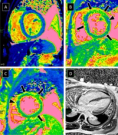

De nombreuses personnes infectées par la COVID‐19 ne présentent que peu ou pas de symptômes. Cependant, la COVID‐19 peut rendre le sang visqueux, obstruant à la fois les petits vaisseaux sanguins (capillaires) et les gros vaisseaux sanguins, ce qui pourrait causer des crises cardiaques, des accidents vasculaires cérébraux ou des caillots sanguins dans les jambes ou les poumons. Ces affections peuvent être fatales. Les personnes souffrant de diabète, d'hypertension artérielle ou de problèmes cardiaques préexistants courent un plus grand risque de développer de telles complications si elles sont infectées par la COVID‐19.

La COVID‐19 et ses effets cardiovasculaires: une revue systématique d’études de prévalence